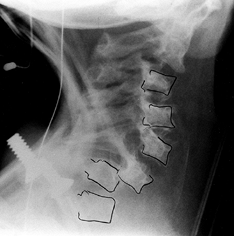

as a “champagne glass” appearance. The radiographic hallmark of the

achondroplastic spine is progressive narrowing of the transverse

interpedicular distance as one measures from cephalad to caudad in the

lumbar spine (Fig. 180.3). The pedicles are thickened, and there may be posterior scalloping of the vertebral bodies.

![]() |

|

Figure 180.3. Progressive interpedicular narrowing in the lumbar spine of a 5-year-old girl with achondroplasia.